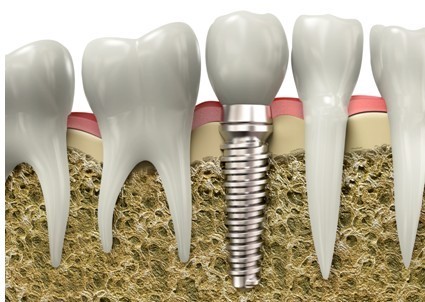

牙齿缺失后的修复方法有三种:

(1)种植牙:将人工材料制成的种植体经手术植入缺牙区的颌骨内,然后在种植体上部完成义齿修复,种植体起着人工牙根的作用。